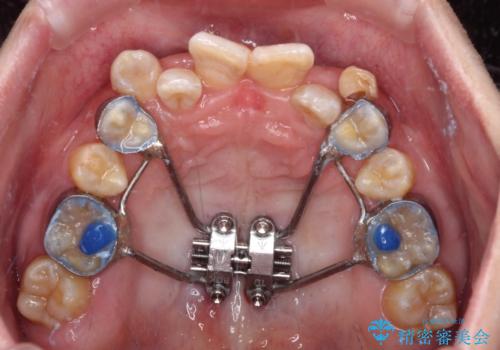

それらを改善するため上顎に拡大装置を用いて、審美装置にてワイヤー矯正を行いました。

上顎が側方に拡大されて歯が並ぶスペースを確保できました。

それに伴い下顎の歯列も拡大され、舌側に倒れているのが改善されました。